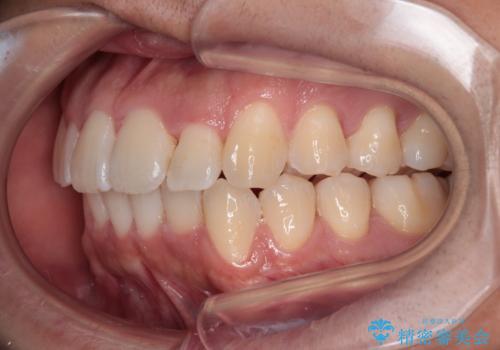

前方に捻れた前歯を治したい インビザライン矯正治療

- 前歯のデコボコを治したいとのことで来院された患者様です。

上下顎ともに歯列全体の後方移動とIPR(歯と歯の間を削る)によってデコボコが解消するように設計し、インビザラインにより治療を行うこととしました。

下顎前歯は後戻りを起こしやすいため、舌側を細いワイヤーで固定し、マウスピース型リテーナーで保定を行うこととしました。